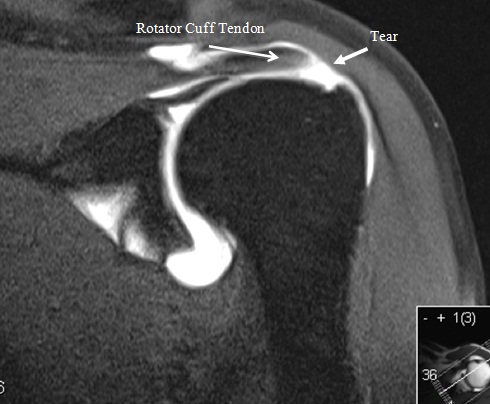

In diagnosing a full thickness tear or a partial thickness rotator cuff tear mr arthrography is more sensitive and specific than either mri or ultrasound p 0 05. With this kind of test a contrasting dye is injected into the shoulder though this dye is different than that used in a standard arthrogram.

Rotator cuff tear mri arthrogram. Tendon retraction may also be present which can be graded using the patte classification. The rotator cuff tendons are fairly thick tendons about as thick as your little finger and wide each one about as wide as three of your fingers. A routine shoulder mri which takes about 25 minutes of actual scan time and shoulder mr arthrogram which involves an x ray procedure during which contrast is injected directly into the.

The presence of a tendon defect filled with fluid is the most direct sign of rotator cuff tear. In some cases an arthrogram can be done using the same technology as a mri radiologyinfo explains. The subacromial bursa serves as a buffer between the rotator cuff and coracoacromial arch and is located below the acromion coracoacromial ligament and above the rotator cuff.

The contrast dye helps outline the muscles and tendons within the rotator cuff. If your doctor does recommend an mri for your shoulder there are two potential types of mri procedures that can be used to diagnose a rotator cuff tear. Indirect signs on mri are subdeltoid bursal effusion medial dislocation of biceps fluid along biceps tendon and diffuse loss of peribursal fat planes.